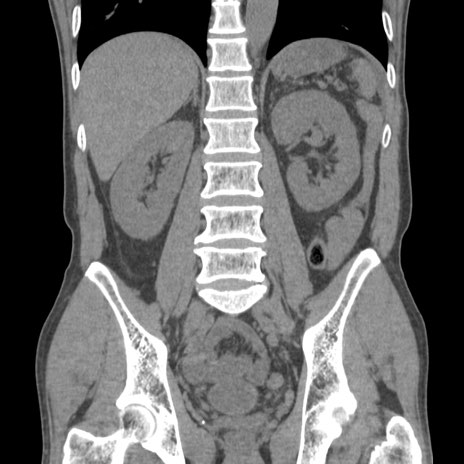

症例56 CT(冠状断像)

脂肪ウインドウ